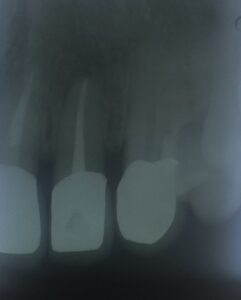

歯根尖端 部分に 肉芽腫様 の 骨吸収像が 観えます。

根管治療が 終わって

2年 経過。

無菌的 根管治療を 行えば

ホラっ!

歯槽骨 回復して きました よっ!